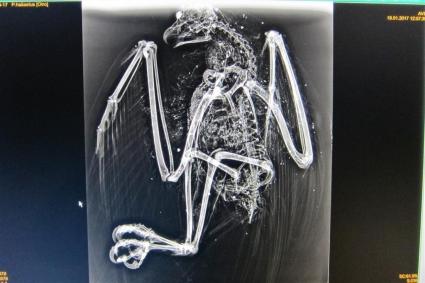

Els vigilants de seguretat de l'aeroport han trobat prop de les instal·lacions aeroportuàries de Palma un exemplar d'àguila peixetera, 'Pandion haliaetus', amb nombrosos perdigons en el seu interior.

L'animal, que està considerat espècie amenaçada, va ser traslladat al Consorci de Recuperació de la Fauna de les Illes Balears (Cofib) on els veterinaris del centre van dur a terme la necròpsia de l'au. El resultat de l'analítica, segons ha indicat la Conselleria de Medi ambient, Agricultura i Pesca, ha desvetllat que es tractava d'una au adulta, en estat de descomposició que duia morta més de 2 setmanes.